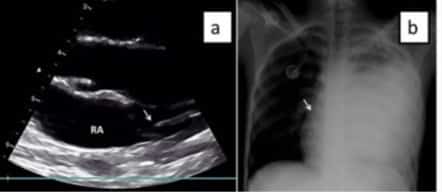

Tras la canalización debe de hacerse una comprobación de la localización de la punta del catéter bien sea por radiografía torácica o por ecografía(más indicado en el caso de los niños), así como la presencia de posibles complicaciones (neumotórax, derrame pericárdico…etc).

Verificación del posicionamiento de la punta del catéter

Esta comprobación es de extrema importancia ya que una localización intracardiaca o demasiado alta puede tener consecuencias graves para el paciente. La comprobación de la localización de la punta del catéter se puede realizar bien por control radiográfico o control de la onda de presión venosa.

La localización ideal de la punta del catéter en el caso de la canalización a nivel del tronco superior seria en el tercio inferior de la cava superior ,mientras que para las canalizadas en el tronco inferior seria a nivel de la unión cavo-atrial.

Para esta exploración se puede usar tanto una sonda lineal como una convex de 2-6 MHz.

Primero se debe descartar la posición intracardiaca. Para ello, se coloca la sonda en la ventana subxifoidea para obtener un plano de cuatro cámaras del corazón. Desde este plano también puede visualizarse si la punta del catéter se ubica a nivel de la unión cavo-atrial. Si no se aprecia a nivel cardiaco el catéter y se aprecia la punta a nivel de la cava superior o unión cavo-atrial -para las de localización inferior- se considera que el catéter esta normo posicionado.

En el caso de que no se visualice la punta del catéter en la cava superior desde subcostal se pasaría a un plano paraesternal derecho o supraclavicular y si a ese nivel no se localiza se considera que el catéter está mal posicionado.